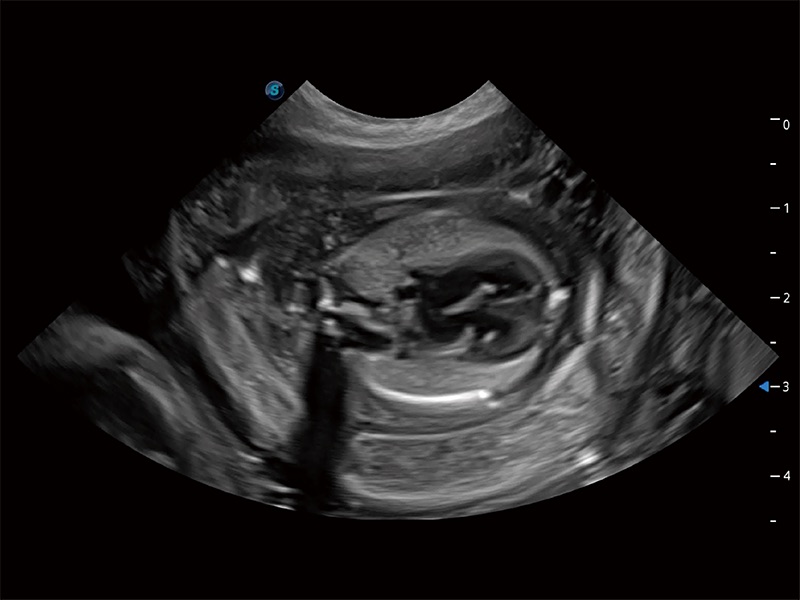

Für alle Kreaturen, ob groß oder klein. Tiere sind die engsten Freunde und treuesten Partner des Menschen. SonoScape hat sich schon immer der Entwicklung von speziellen Lösungen für die diagnostische Bildgebung in der Tiermedizin verschrieben. SonoScape beginnt eine neue Phase in der Ultraschallbildgebung und bringt die brandneuen der ProPet-Serie auf den Markt, die professionelle veterinärmedizinische Lösungen für eine Vielzahl von Tierarten bieten, von kleinen Haustieren bis hin zu Großtieren. ProPet 80, das Premium-Ultraschallsystem für die Veterinärmedizin, nutzt modernste Ultraschalltechnologie für schnelle Diagnoseinformationen, fortschrittliche Funktionen und ein ergonomisches System, um die steigende Zahl schwieriger Fälle und die immer vielfältigeren Anforderungen an die Tierarztpraxis in allen Bereichen zu bewältigen. Es ist in der Tat eine Überlegung wert, wenn Sie ein krankenhausbasiertes Gerät benötigen, das sich für den High-End-Ultraschall eignet.

Deckt zahlreiche Anwendungsbereiche ab, beispielsweise Reproduktion, Herz und Bewegungsapparat, und bietet die notwendigen Werkzeuge für die Bedürfnisse des Anwenders, einschließlich tierartspezifischer Formeln wie Cornell und Körperoberfläche.